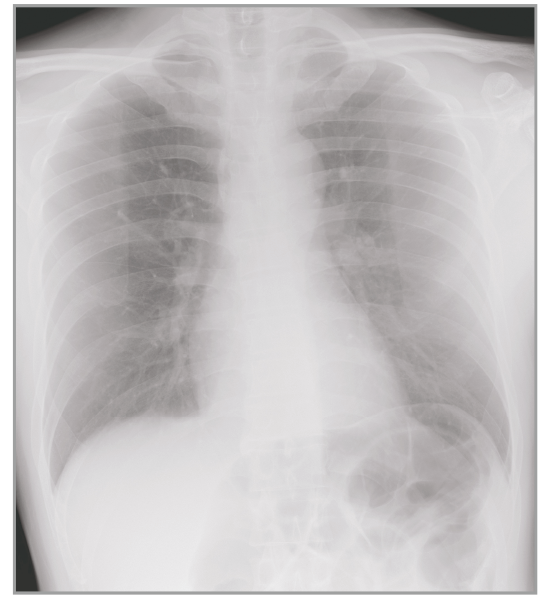

Dynamic Visualization II

Optimizes image quality using latest Exposure Data Recognizer

Advanced recognition algorithms using automatic  calculations of estimated 3D image data, identify the body part required and adjusts contrast, density and enhancement for optimised image display. (Option)

Comparison of Dynamic Visualization II vs. conventional processing images (Lumbar Spine)